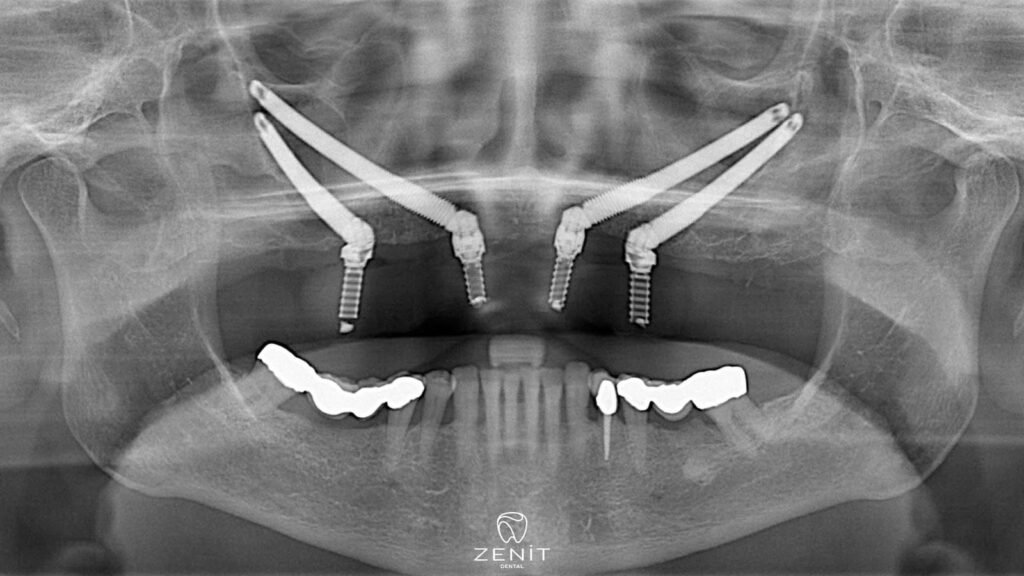

Zygoma-Implantate bieten eine hervorragende Alternative für Patienten mit unzureichendem Kieferknochen und bieten eine revolutionäre Behandlung im Gesichtsbereich. Diese speziellen Implantate werden im Gegensatz zu herkömmlichen Implantaten in den Jochbeinknochen (Zygoma) und nicht in den Oberkieferknochen eingesetzt. Da der Jochbeinknochen eine dichtere und stärkere Struktur aufweist als der Kieferknochen, können Jochbeinimplantate in diesem Bereich sicher eingesetzt werden. Dank Zygoma-Implantaten können auch Patienten mit fortgeschrittenem Knochenschwund ästhetisch und funktionell zufriedenstellende Ergebnisse erzielen.

Zygoma-Implantate, die im Wangenknochen eingesetzt werden, werden im Gegensatz zu anderen Zahnimplantaten nicht im Kieferknochen, sondern im Bereich des Jochbeins platziert, der sich in der Mitte des Gesichts befindet und eine sehr solide Struktur aufweist. Der Jochbeinknochen hat eine dichtere Struktur als andere Knochen und Knochenverlust tritt normalerweise nicht auf. Dank dieser Funktion bieten Zygoma-Implantate eine sichere und wirksame Lösung für Patienten mit Kieferknochenmangel.

• Implantatinsertion: Zygoma-Implantate werden im Wangenknochen statt im Oberkieferknochen eingesetzt. Beim Einsetzen der Implantate arbeitet der Chirurg mit hoher Präzision, denn das Erreichen des Jochbeinbereichs und das Einsetzen der Implantate in die richtige Position erfordert große Sorgfalt.